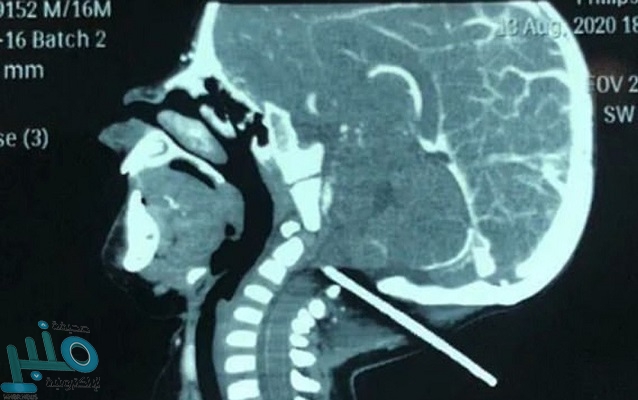

وكان الرضيع البالغ من العمر عاماً واحدًا، سقط إلى الوراء على قضيب معدني مثبت بفتحة غطاء، مما تسبب في اختراق القضيب الجمجمة من الخلف؛ حسبما ذكرت صحيفة ”ديلي ميل“ البريطانية.

وذكر التقرير، أن الطفل نقل على الفور إلى أحد المستشفيات فى مدينة جينان بمقاطعة شاندونغ، وكشف عن استقرار حالة الرضيع بعد خضوعه لعملية استغرقت ساعة، استطاع خلالها الفريق الطبي إزالة القضيب الحديدي من رأسه.

وقال الدكتور وانغ جوانغ مينغ رئيس قسم جراحة الأعصاب في مستشفى الأطفال، إن حالة الطفل كانت حرجة وقت حضوره، وبفحصه وجدوا أن القضيب كان على بُعد خمسة ملليمترات من ثقب الأوعية الدموية، مما قد يسبب نزيفًا يهدد حياته، لكن سارت الأمور على ما يرام ونجحت العملية الجراحية، ونجا الطفل.